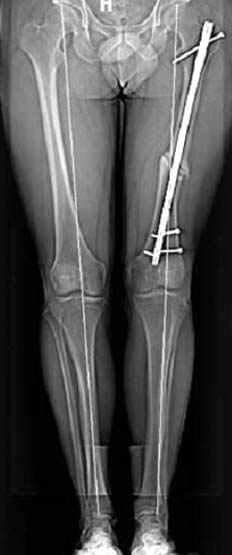

Несколько снимков из моей коллекции, чтобы разьяснить, почему мы до сих пор делаем различные варианты остеотомии.

На рисунке N1 предоперационный план лечения ложного сустава шейки бедра- линия ложного сустава, угол и направление введения импланта, клиновидная остеотомия в градусах и миллиметрах, второй снимок после коррекции, расчет, на сколько удлиняется конечность и размеры импланта;

N3 рисунок окончательный снимок, после операции моя рентгенограмма должен выглядеть примерно как эта картина. На N4 снимке клин перед удалением; N5 послеоперации 3 нед.; N6 окончательная рентгенограмма.

(доложен в Ст. Петербурге 2003 и в Москве 2004)

варус при проксимальном отделе 95 градусной пластиной.

Интересно бы посмотреть рентгенограмму таза (оба сустава) а также рентгенгорамму с захватом коленных суставов (по Dror Paley).